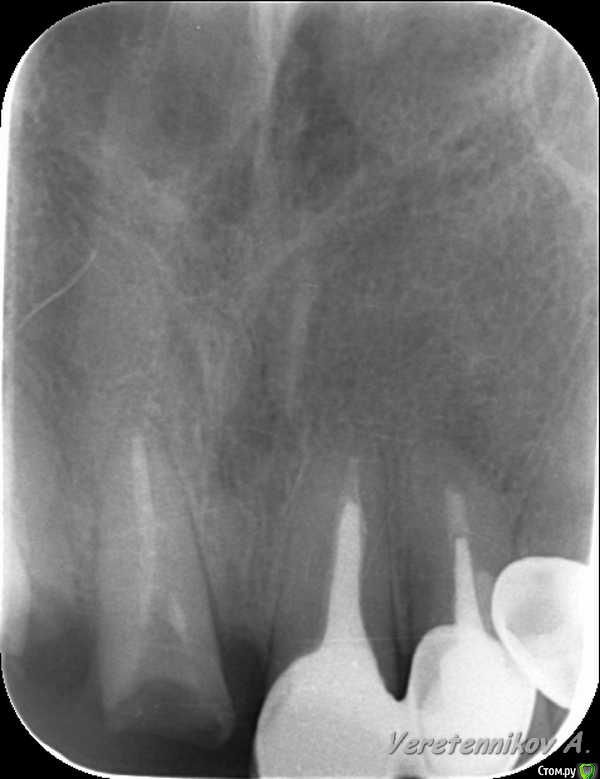

an_ver Опубликовано 26 марта, 2015 Поделиться Опубликовано 26 марта, 2015 (изменено) 11,12..11 трещина корня,вест.часть,12 рыхло все..сгнило.Убрал,кюретаж,11 вест. стенки нет на 2/3.Установил 11-4,2*13;12-3,75*13 мм..все Альфа.Мп3,мембрана эволюшн.11 заглушил,12-временный абатмент,коронка.Шил викрил 4,0. Фсе...пинайте Изменено 26 марта, 2015 пользователем an_ver 7 Ссылка на комментарий

Фарид Расулыч Опубликовано 26 марта, 2015 Поделиться Опубликовано 26 марта, 2015 Пациент с "шикарным" ртом))))) Все хочу так же попробовать времянки завремянить, но постоянно забываю снять слепок до удаления... лошпэ я.. Ссылка на комментарий